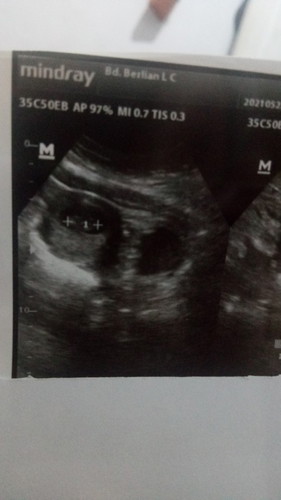

Bun...td aku abis usg uk9week....alhamdulillah udah ada janinnya dan smua keadannya sehat....tp td kata bu bidan itu sblh ktg rahim ada lubang item jg...dan kty srh usg k dktr apesialis kandungan cz tkt miom atau kista gt....aku takut bgt ini bun malah jd kpikiran...kira2 itu apa y bun....bunda ada yg prnh nglamin gini jg ga?trs kira2 berpotensi ngaruh k janinnya sbrp besar bund#seriusnanya #bantusharing #ingintahu #jangandibully